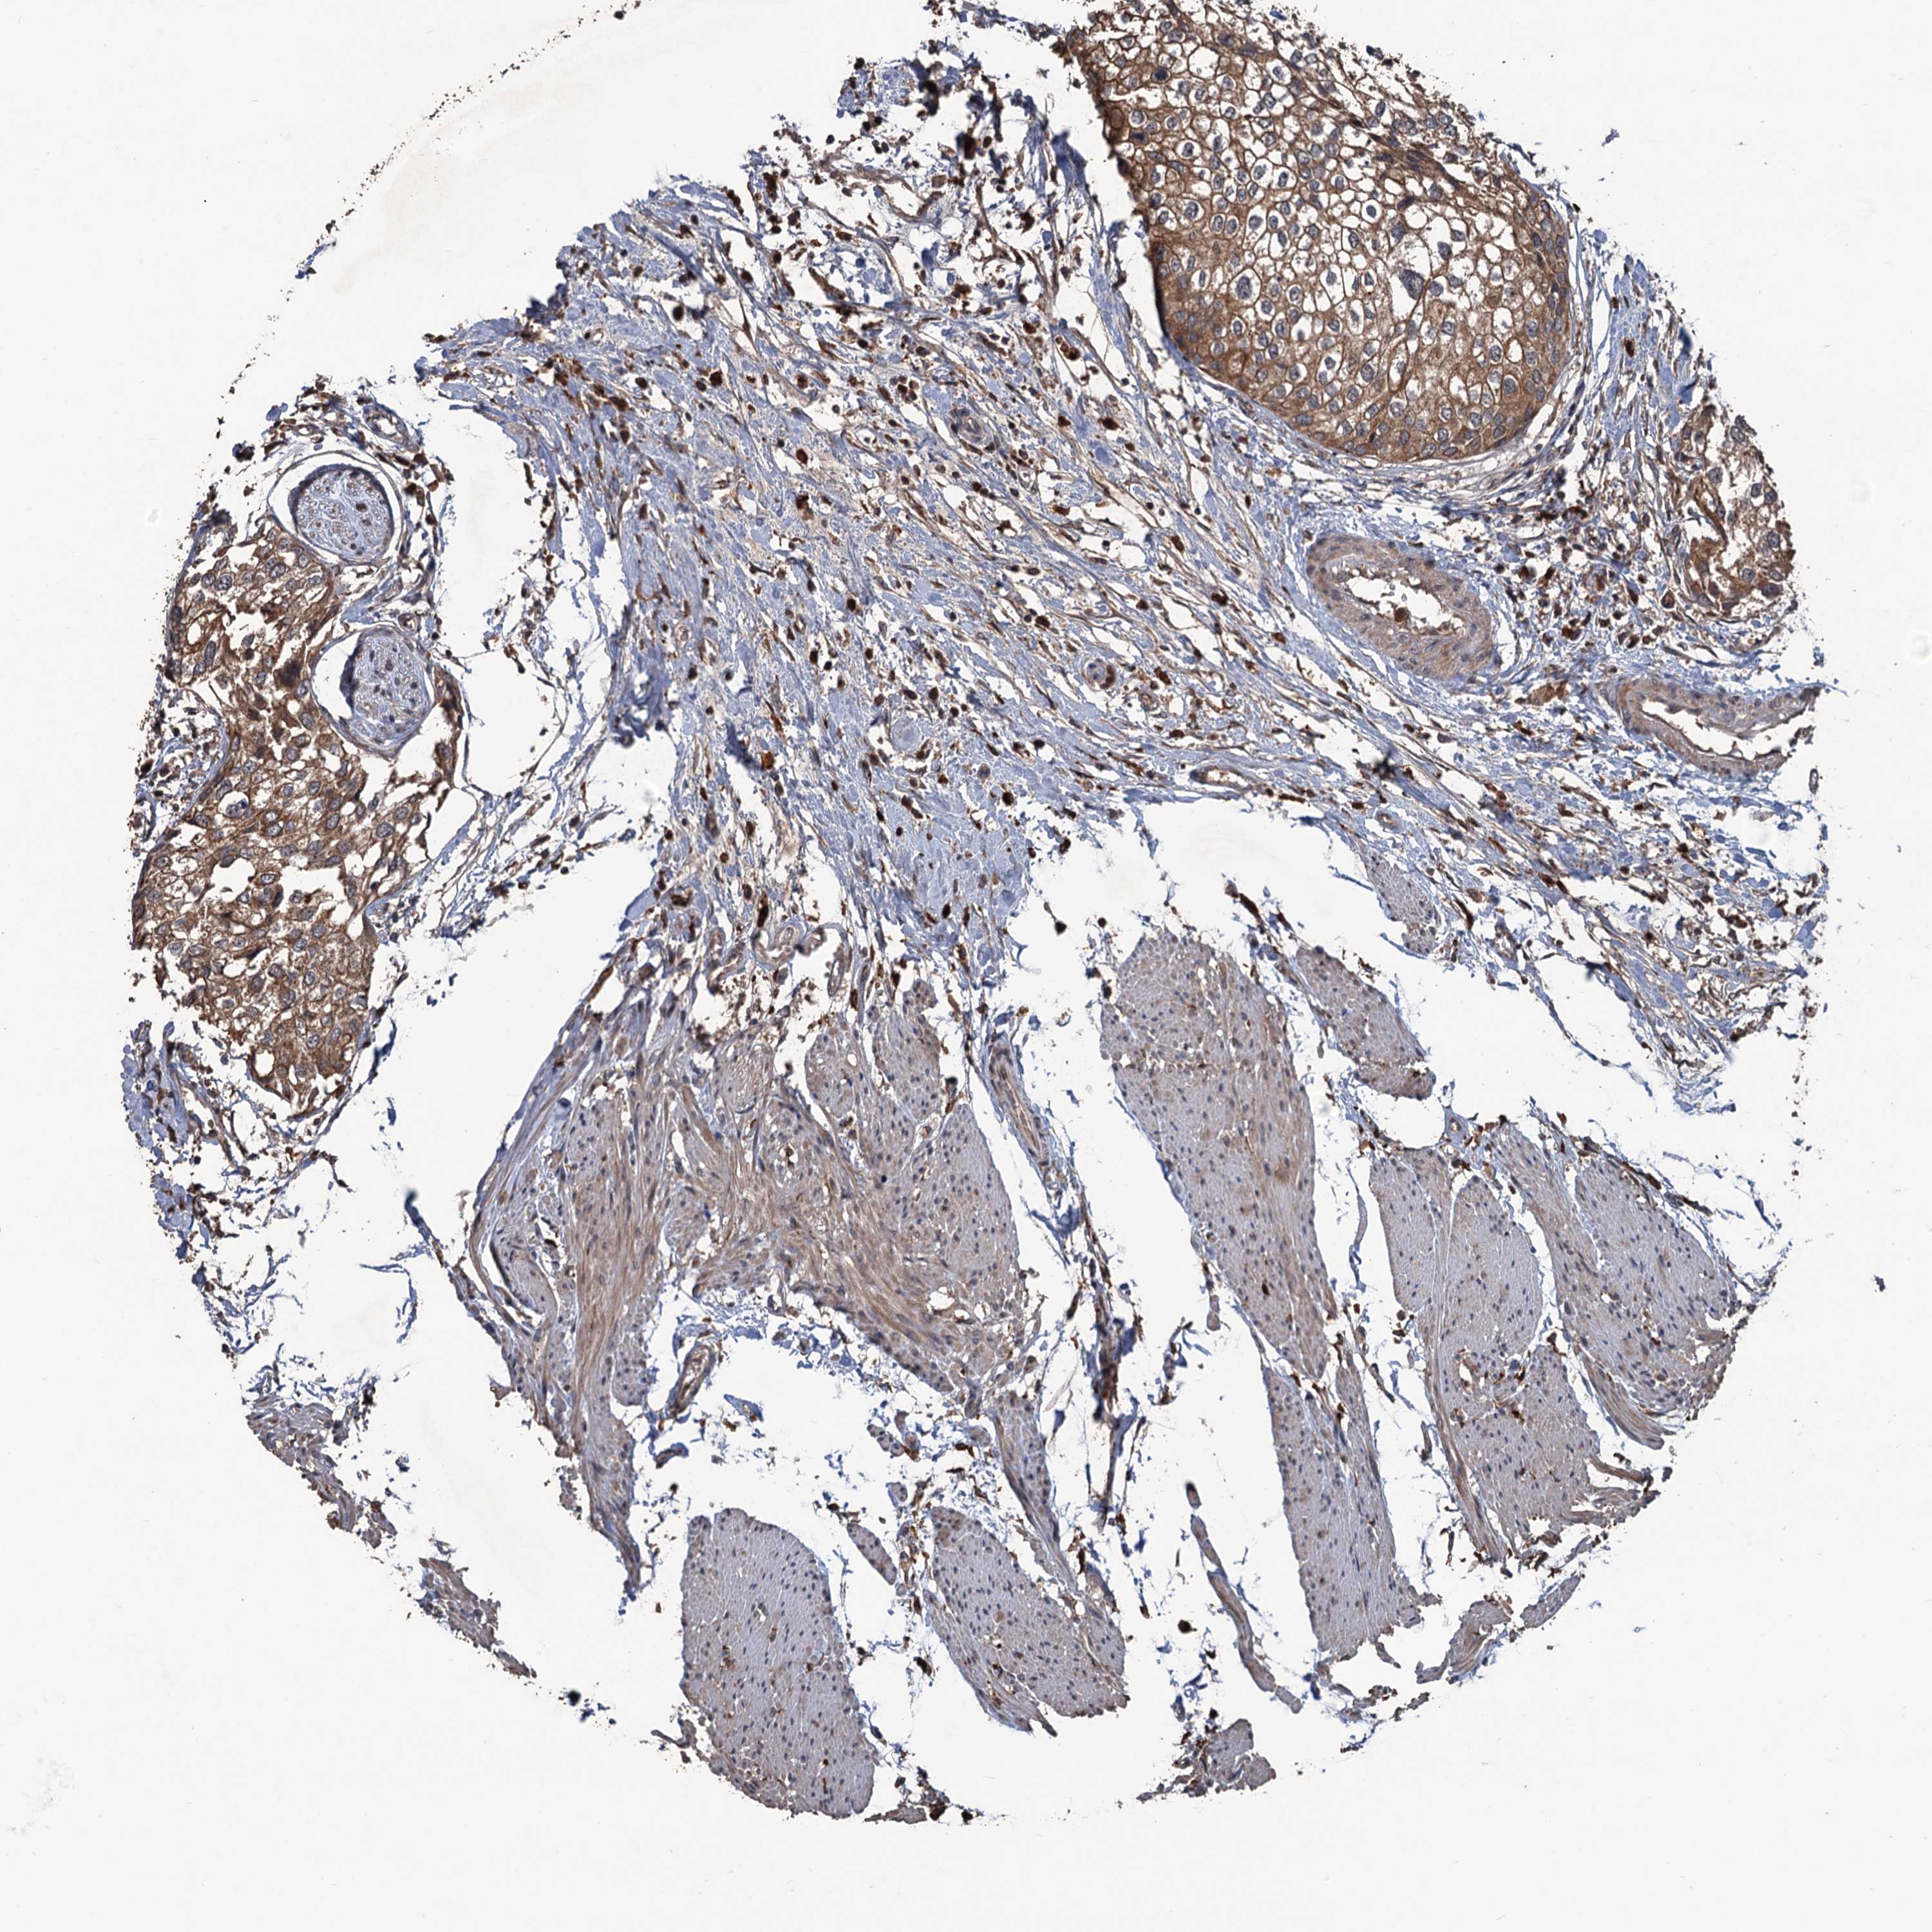

UROTHELIAL CANCER - Protein expressioni

A mouse-over function shows sample information and annotation data. Click on an image to view it in a full screen mode. Samples can be filtered based on level of antibody staining by selecting one or several of the following categories: high, medium, low and not detected. The assay and annotation is described here.

Note that samples used for immunohistochemistry by the Human Protein Atlas do not correspond to samples in the TCGA dataset.

Antibody stainingi

Antibody staining in the annotated cell types in the current human tissue is reported as not detected, low, medium, or high, based on conventional immunohistochemistry profiling in selected tissues. This score is based on the combination of the staining intensity and fraction of stained cells.

Each image is clickable and will lead to virtual microscopy that enables deeper exploration of all samples and also displays staining intensity scores, fraction scores and subcellular localization as well as patient and tissue information for each sample.

Antibody HPA039843

Staining

High

Medium

Low

Not detected

Intensity

Strong

Moderate

Weak

Negative

Quantity

>75%

75%-25%

<25%

None

Location

Nuclear

Cytoplasmic/membranous

Cytoplasmic/membranous,nuclear

Urothelial carcinoma, High grade

Urothelial carcinoma, Low grade